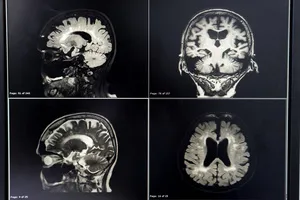

알츠하이머와 치매 차이

| 구분 | 알츠하이머병 | 치매 |

| 원인 | 뇌세포 손상 | 혈관성 질환, 뇌종양, 뇌염 등 |

| 진행 속도 | 서서히 진행 | 상대적으로 빠르게 진행된거나 단계적으로 진행 |

| 초기 증상 | 기억력 저하, 언어 능력 저하 | 기억력 저하 외에도 갑작스러운 혼미, 마비, 감각 이상 등 |

| 뇌 영상 검사 소견 | 특징적인 뇌 위축 소견 | 뇌경색, 뇌출혈 등 혈관성 병변 |